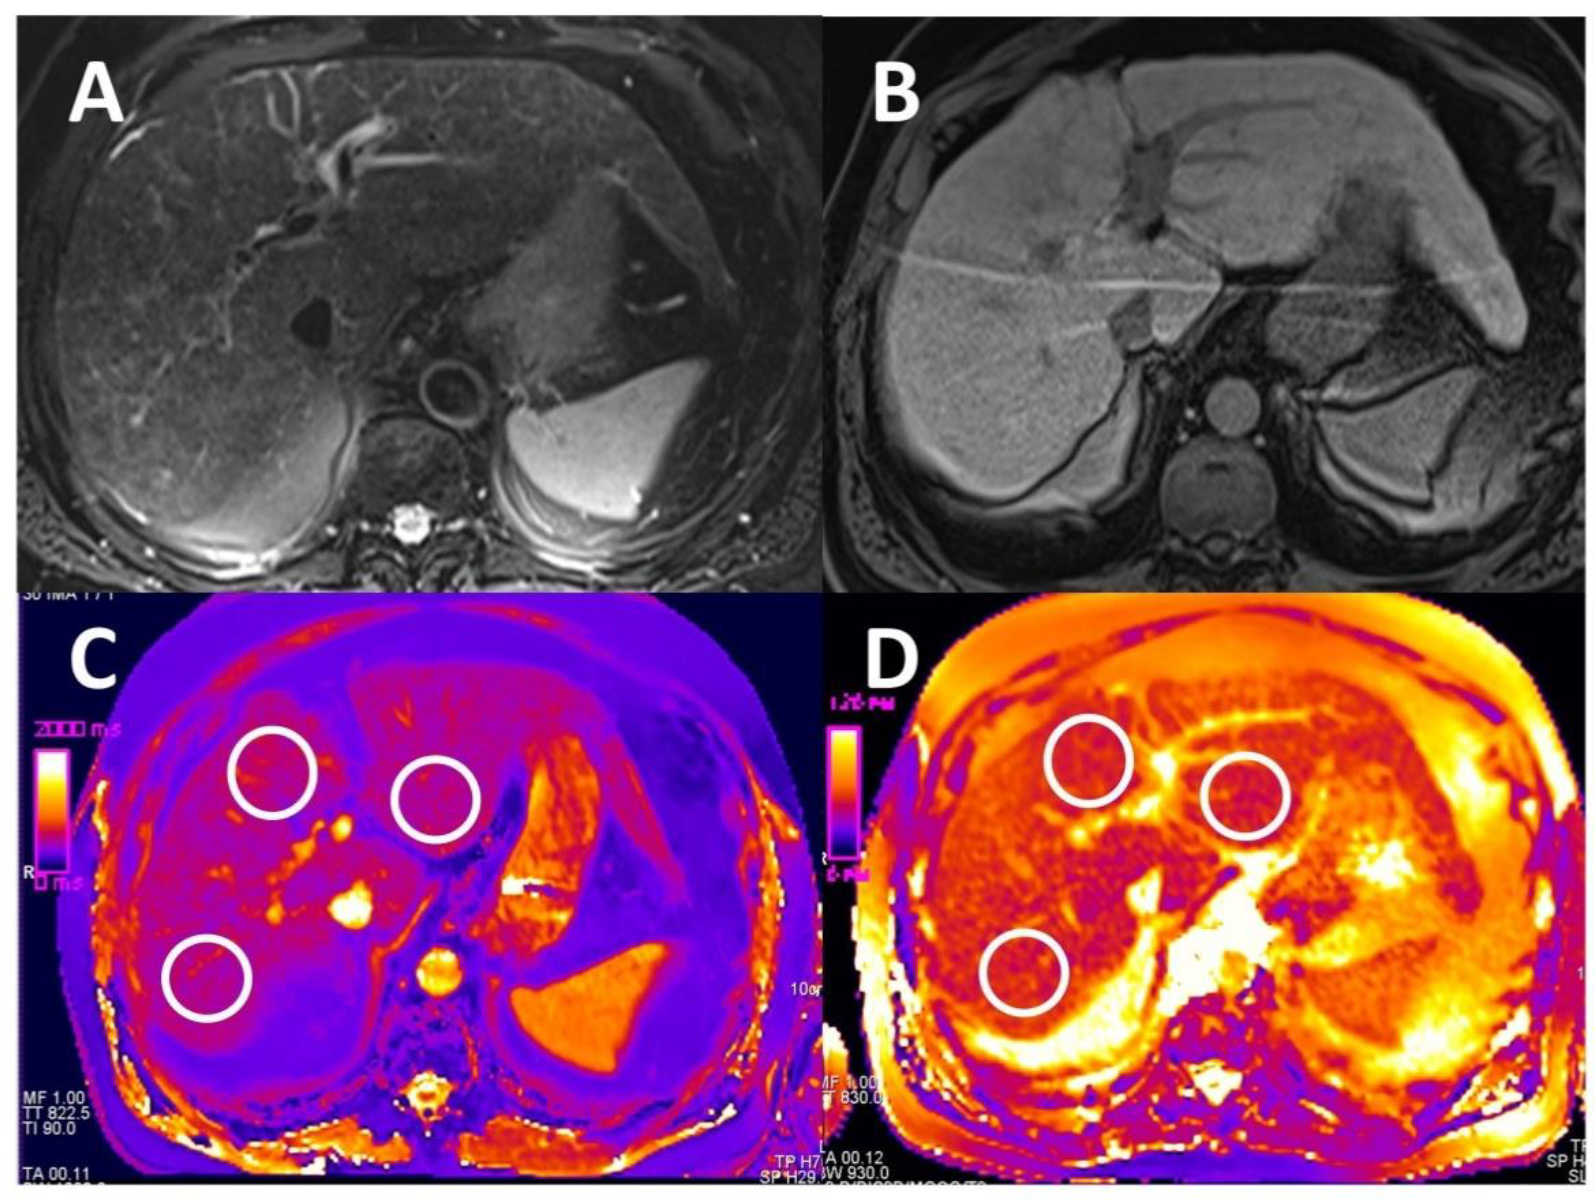

2.4.1. T1 and T2 Relaxometry